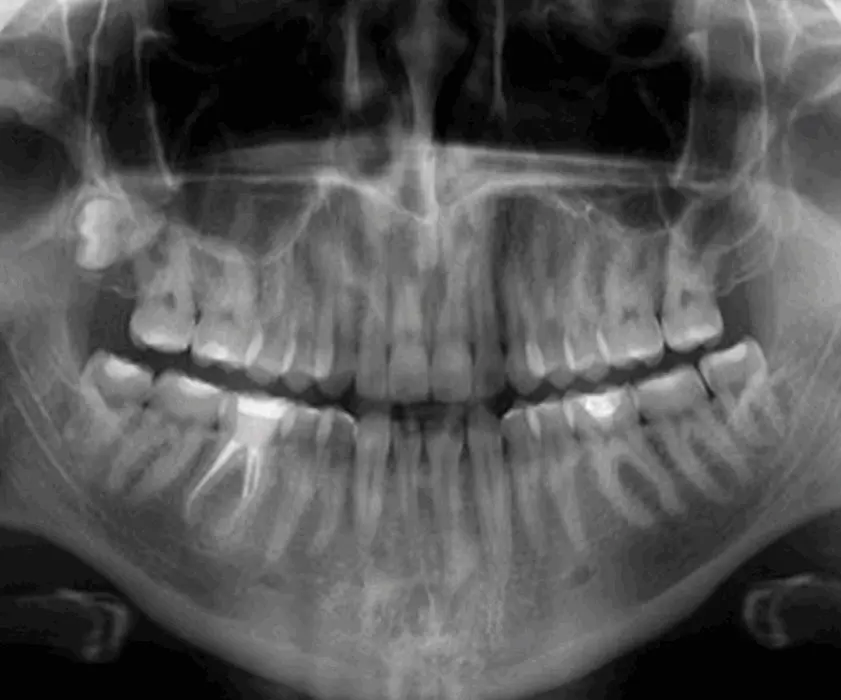

Panoramskom snimkom vrlo brzo je vidljiv uzrok boli i otoka te prilikom dijagnostike doktor dentalne medicine predlaže terapiju. U stomatološkoj poliklinici Štimac u Zagreb, Filip Štimac, dr.med.dent., specijalist oralne kirurgije detaljno će Vam objasniti zahvat cistektomije i što možete očekivati nakon zahvata.

Zubne ciste su šupljine obložene tkivom te se mogu pojaviti u zubnoj čeljusti ili mekom tkivu (npr. u obrazima). Zubne ciste nastaju posljedica na konstantnu infekciju koja se pojavljuje na vrhu korijena. Inficirani zubi najčešće se javljaju uslijed loše oralne higijene ili netretiranja karijesa na vrijeme.

Ukoliko se dijagnosticira jedna od navedenih promjena, potrebno je u što kraćem roku ukloniti nastalu promjenu kako ona ne bi rasla te se proširila na susjedne zube. Ne tretiranjem promjena zubna struktura može oslabiti, oštetiti zdrave zube, zahvatiti sinus i nos te uzrokovati velike upale na licu.